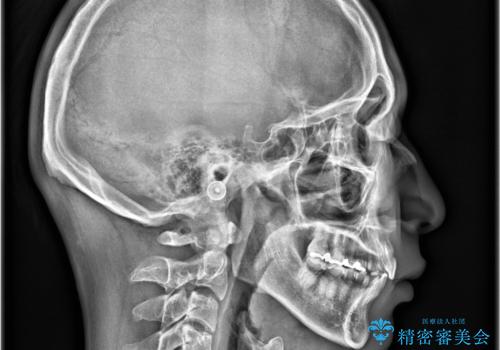

- 「上の前歯の捻じれと下の前歯のでこぼこを治したい」を主訴に来院された患者様です。

矯正検査の結果、非抜歯で矯正可能だったためインビザラインで治療を行いました。

アーチの拡大とIPRで叢生を改善いました。

11ヵ月で矯正を終える事ができ患者様も大変ご満足されていました。